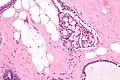

Collagenous spherulosis is characterized by a tubular/cribriform architecture with intratubular eosinophilic material that classically is arranged like the spokes of a wheel ("radial spikes"). There is usually no mitotic activity, and two cells populations (epithelial & myoepithelial) are present, like in benign breast glands.

The lesions are typically small (less than 50 spherules per lesion, less than 100 micrometers in size) and may be multifocal.

Intermed. mag.